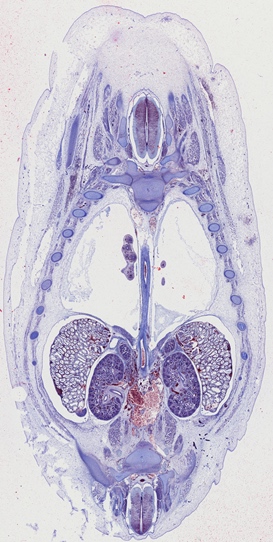

For almost two decades, we have provided prepared slides suitable for various biomedical courses. These glass slides contain sectioned, mounted, or smeared tissues stained with different methods.

They can be used to study histology, pathology, oral histology, oral pathology, embryology, microbiology, parasitology, and hematology.

Click the following categories to view example photos taken from these prepared slides.

The representative photos shown in each category are examples taken under the light microscope. They may not be the same ones as those available for your need. Complete lists of prepared slides for each course can be downloaded for further consideration.